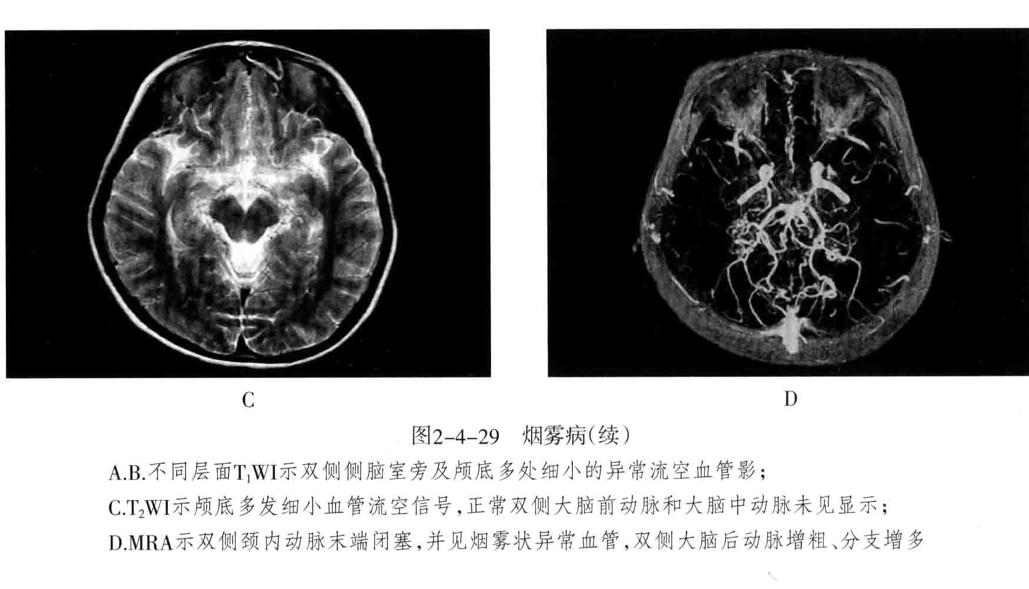

十、烟雾病

又称为脑底异常血管网症、脑底动脉环闭塞症。是以脑内虹吸段至大脑前、中动脉近端狭窄或闭塞,同时伴有广泛侧支循环形成,导致颅底出现异常毛细血管网为特征的脑血管病。好发年龄10岁以下和40-50岁。临床表现为脑缺血和脑出血两大类。儿童多为颈内动脉系统缺血性改变,成人多为颅内出血。

1. CT平扫表现为双侧额叶、顶叶及颞叶皮质或皮质下区多发脑梗死及脑萎缩改变,也可以出现颅内出血。增强有时可见到颈内动脉及大脑前中动脉粗细明显不对称,或者充盈不良,甚至不显影。可显示基底池及基底节区的侧支循环网,大多表现为为不规则的扭曲成团的强化血管影。

2. MRI表现为脑缺血引起的T1WI低、T2WI高信号脑梗死区,颈内动脉及大脑中动脉主干的“流空效应”变弱或消失,异常血管网在T2WI上表现为基底节区和鞍上池内多发细小血管影,呈网状低信号或无信号区。皮质侧支循环形成时,增强扫描可见皮质血管增多、扩张、强化、呈“常春藤征”。

3. MRA可直接显示颈内动脉、大脑前、中动脉狭窄或闭塞,于颅底见烟雾状异常血管网,常可见到颈外动脉和椎-基底动脉分支代偿性增粗。

4. 脑血管造影是确诊烟雾病的主要检查方法,可显示狭窄或闭塞的动脉及异常扩张的血管网。